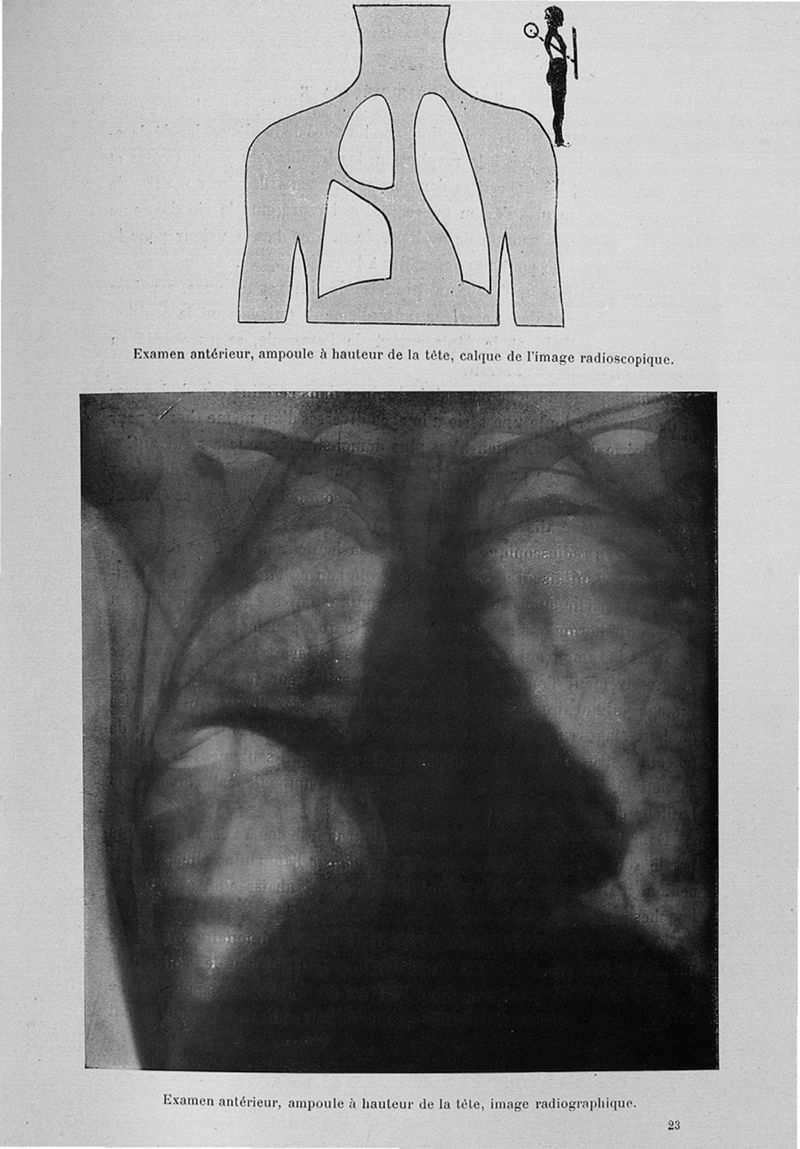

Béclère, Antoine Louis Gustave.

Exposé des travaux scientifiques

Paris, Masson, 1907.